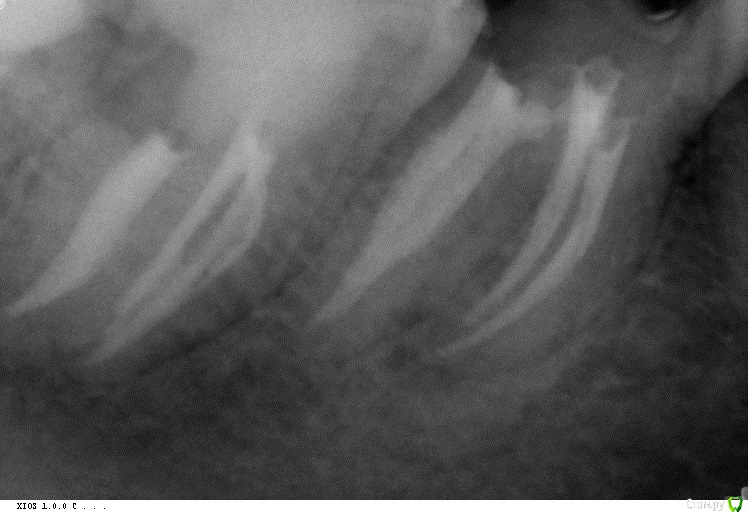

Audutor Опубликовано 14 июля, 2016 Поделиться Опубликовано 14 июля, 2016 (изменено) А вообще надо сказать что реципрок недооценен, в том контексте что может быть опилки и толкает. Но зато дает тонну времени для ирригацииhttps://www.facebook.com/zaher.altaqi/videos/vb.100000373036337/1005090786180013/?type=2&theaterКогда увидел впервые, был в легком шоке)А сейчас понимаю что за этим будущее)Видео специально показывают что даже без ирригации такое возможно..., само собой это не сложная анатомия итд итп. С другой это всетаки МБ2 Изменено 14 июля, 2016 пользователем Audutor Ссылка на комментарий

Kolchanov Опубликовано 15 июля, 2016 Поделиться Опубликовано 15 июля, 2016 Это очень жирный МВ2 и к тому же обработанный МВ1. Любой активный файл забурится туда так же. Ссылка на комментарий